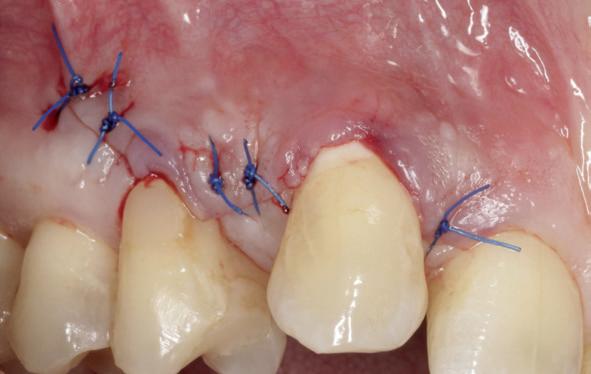

Stap 5: Teflon aanbrengen

Pak één centimeter Teflon tape en prop dit aan de tegenoverstaande zijde van waar de wig zich bevindt. Je doet dit met een bij de punt platgeslepen Sikkelsonde. Gebruik van Teflon tape zorgt voor een perfecte adaptatie en afsluiting van de matrixband, zelfs bij furcaties (afbeelding 8 en 9).

Stap 6: Vullen

Zorg ervoor dat je allereerst de bodem en opstaande wanden van de preparatie vult, zodat je met een Ash 49 de matrixband mooi tegen het buurelement kan forceren. Als de knobbels genoeg ‘body’ hebben, kan de separatiering geplaatst worden voor een mooi contactpunt (afbeelding 10).